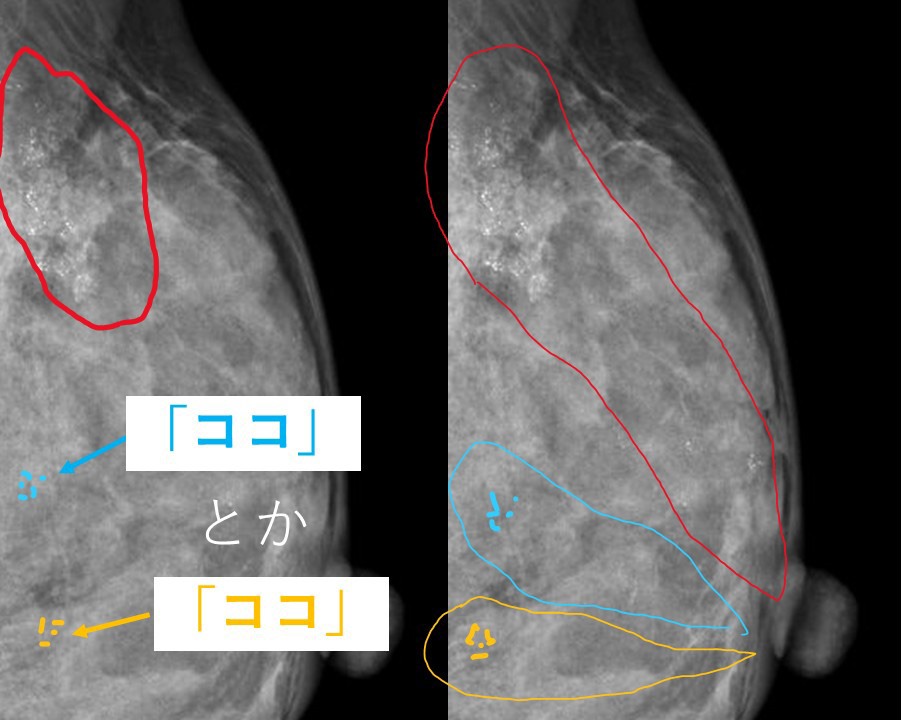

私が文面から想像していた石灰化

1.真の意味で多発

石灰化 「赤色」 「水色」 「黄色」 これらの石灰化は「全く別々の区域」であり

互いに「無関係」 つまり真の意味で「多発」

つまり、私が事前に回答していた「別の石灰化も癌なのか、そららのまずは1か所だけでも(ST-MMTで)確認する」

というのは(図の赤色の石灰化が癌と診断されていたとして)上図の「水色」もしくは「黄色」のどちらかでもST-MMTをしてみて

もしもそれ(水色ないし黄色)も癌であれば、「真の意味の多発=温存不適切」と判断できる。

という意味だったのです。

ところが実際には…

2.(多発ではなく)同じ乳管系の中の「複数の石灰化」だった!のです。

(実際の画像)

前医では、なんと(赤枠で囲った)main lesionの他に(その中枢側に)「黄色枠」や「青枠」の部分の石灰化を「多発=温存不可」と説明していたのです!

明らかにこれら(「黄色枠」や「青枠」)は「赤枠」と同じ乳管系の「中枢」にできた石灰化であり、多発ではなく「同一乳管系の複数の石灰化」と呼ぶべきものだったのです!